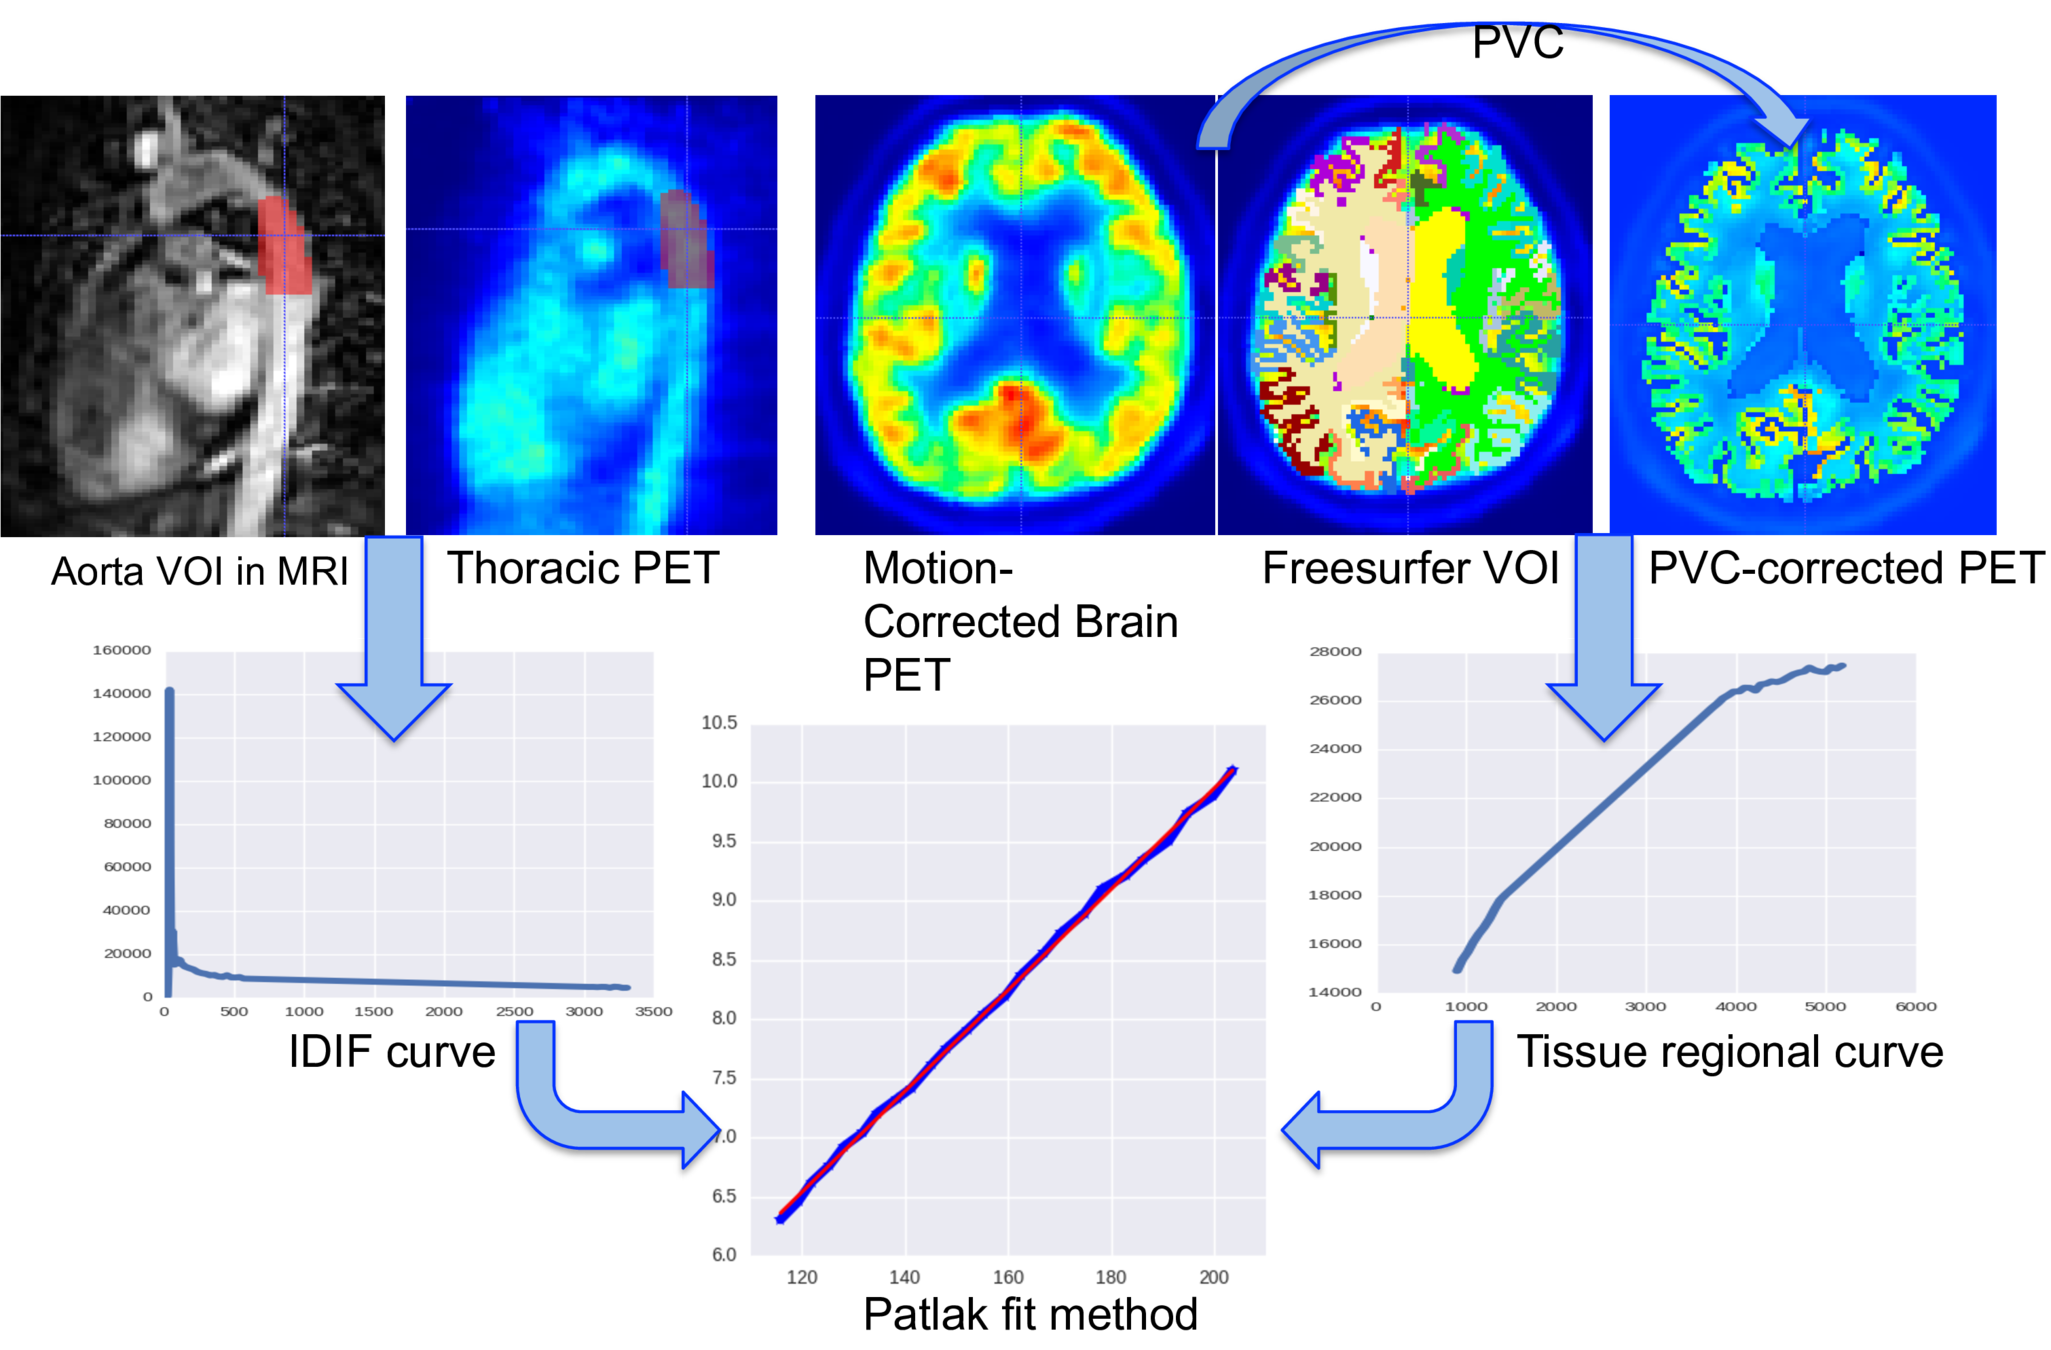

4. Glucose PET/MRI in MS

29 patients, 14 CIS/eRRMS and 15 RRMS underwent a PET/MRI with:

- MRI sequences: 3D T1, 3D FLAIR, 3D DIR

- 18F-Fdg PET in list-mode

The aim is to study the relationship between:

- aMRGlu

Results:

CIS/eRRMS differed significantly:

- 0/66 cortical areas in CTh

- 33/66 cortical areas in aMRGlu

- 10/66 cortical areas lesion Number

- 10/66 cortical areas lesion Volume

No correlation was demonstrated between CTh and WM and GM lesion load

No correlation was found between global and regional aMRglu and CTh.

aMRglu correlated with lesion load

Inverse correlation was found between:

- the total number of focal lesions (WM+GM lesions) and the global cortical aMRglu (R=-0.36 e p=0.04)

- WM lesion volume and number and cortical global aMRglu (R=-0.4 and p=0.02 for both)

-

GM lesion number with global aMRglu (R=-0.36, p=0.046)